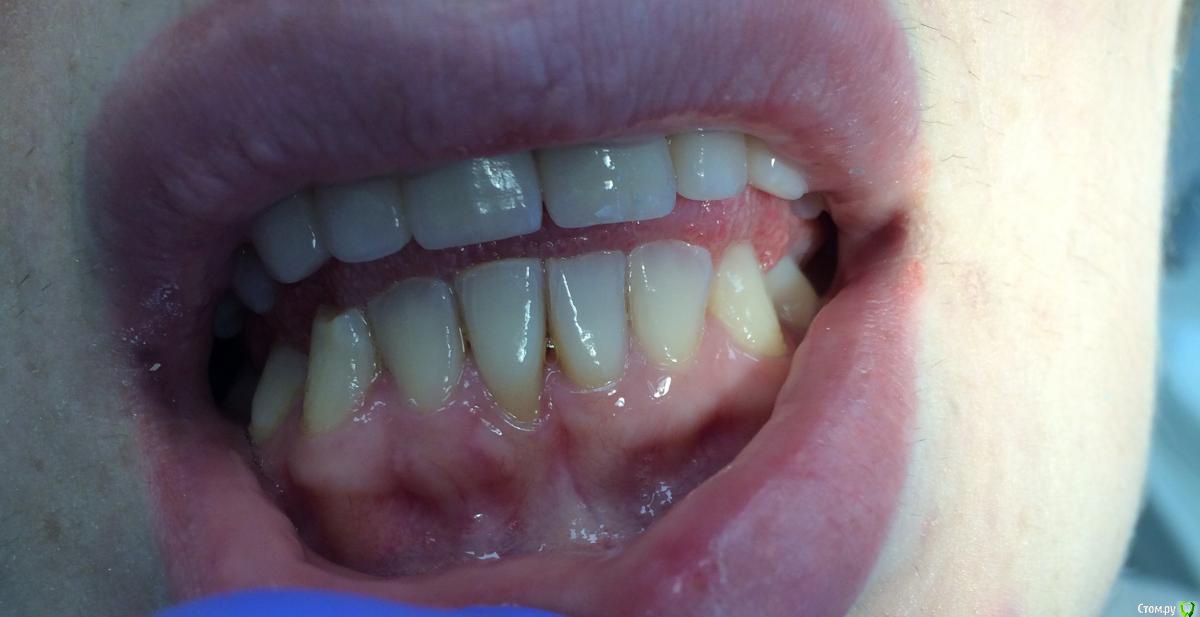

Кариес+ Опубликовано 19 октября, 2015 Автор Поделиться Опубликовано 19 октября, 2015 (изменено) Чтобы не плодить тем , решил спросить тут , планирую закрыть конвертом, правильная тактика или лучше выбрать коронально смещенным лоскутом ? Изменено 19 октября, 2015 пользователем Кариес+ Ссылка на комментарий

Bier Опубликовано 19 октября, 2015 Поделиться Опубликовано 19 октября, 2015 я бы выбрал тут скорее латеральный смещенный из области соседнего зуба. Ссылка на комментарий

Mane Опубликовано 20 октября, 2015 Поделиться Опубликовано 20 октября, 2015 Можно и тоннельно Ссылка на комментарий

carloss Опубликовано 20 октября, 2015 Поделиться Опубликовано 20 октября, 2015 я бы выбрал тут скорее латеральный смещенный из области соседнего зуба. Только взглянув на фото, у меня тоже такая мысль возникла.. но если приглядеться, кератинизированная полоска на соседнем зубе тоньше чем требуется для латерального смещения 2 Ссылка на комментарий

Bier Опубликовано 20 октября, 2015 Поделиться Опубликовано 20 октября, 2015 Только взглянув на фото, у меня тоже такая мысль возникла.. но если приглядеться, кератинизированная полоска на соседнем зубе тоньше чем требуется для латерального смещениясогласен, смотрел с айпада Ссылка на комментарий